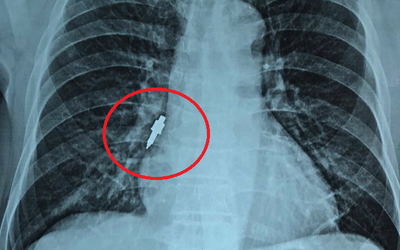

Người đàn ông 33 tuổi bỗng lạnh toát người, bác sĩ phát hiện sự thật "đáng sợ" bên trong bụng

Một người đàn ông đặt mua gần 3kg thạch vị cola về ăn không ngờ bị đổ mồ hôi, cơ thể lạnh, huyết áp cao, đến viện bác sĩ sốc ngang khi biết nguyên nhân.